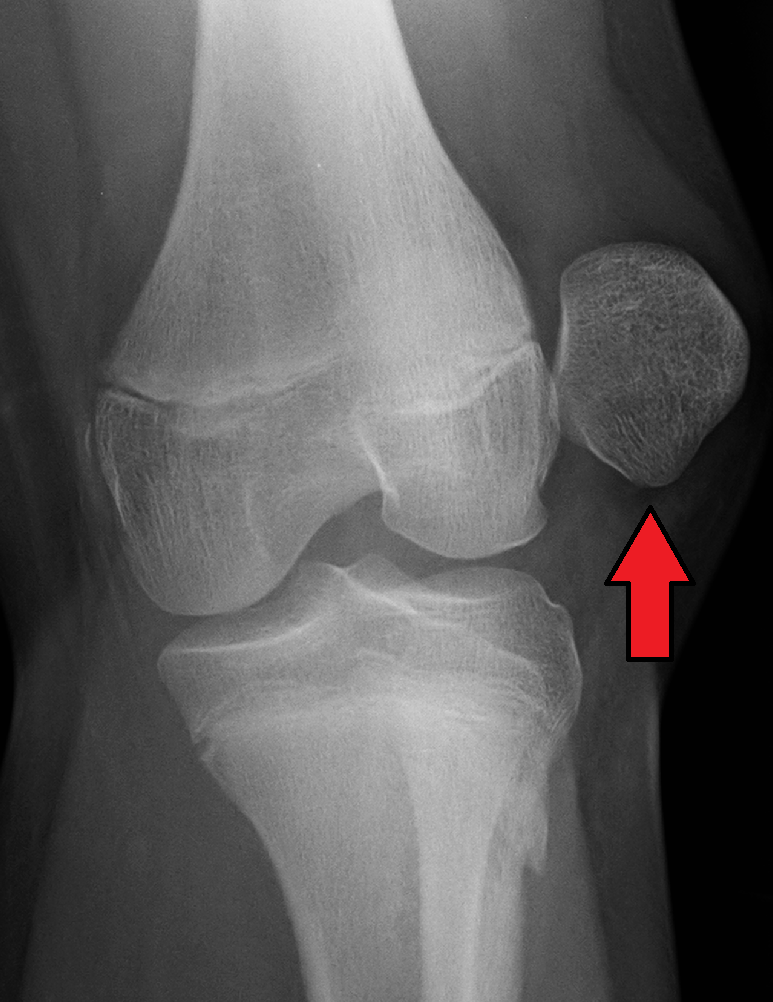

26 year old work comp injury dislocated L patella

While on clinical I worked with a patient who dislocated his left patella lifting a box at work. Upon his first treatment he was wearing a knee brace with a patella support and had a 10# lifting. He had swelling and minimal bruising. The patient had pain with long bouts of standing and starts. I started his treatment session with a 10min warm up on an upright bike. After the warmup I moved to the leg press the patient was nervous at first due to fear of redislocation. I had to progress slowly allowing some room for the patient to become more comfortable. I gave him a HEP of mini lunges, mini squats, marching, and side marching. Progressing the exercises with reps, sets and intensity. After exercises I ended with ultrasound to the medial knee to promote healing and reduce pain. As he progressed he had reports of no pain and had been cleared by his doctor to use a less supportive brace when working. I then moved to funcinal return to work activities. I instructed him in lifting a crate with weights with proper body mechanics. Along with pushing and pulling and overhead reaching exercises. This was progressed as tolerated, safely increasing the weight. With the goal to improve strength and stability with education on posture and proper body mechanics upon returning to work.